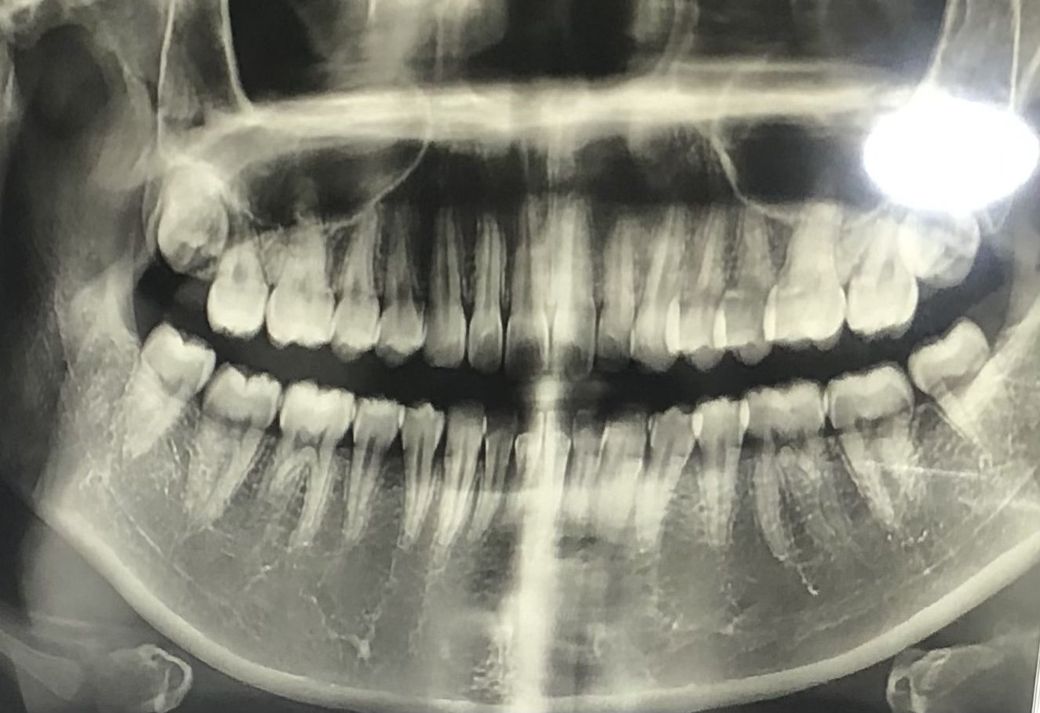

사랑니 발치 해도 괜찮을까요?

사진은 작년 11월 찍은거여서 지금은 세 개는 나왔고 오른쪽 윗 사랑니는 나오고 있는 중이에요.

근데 나오는 과정에서 통증이 심하길래 치과 두 곳을 가봤더니 두 병원 모두 4개의 위치가 안좋아서 모든 사랑니를 빼자고 하셨어요.

혹시 신경과 맞닿아있어서 감각 이상 등의 증상이 있을 지..그리고 빼도 괜찮은 사랑니들인지? 궁금합니다.

• 1번 째 사진